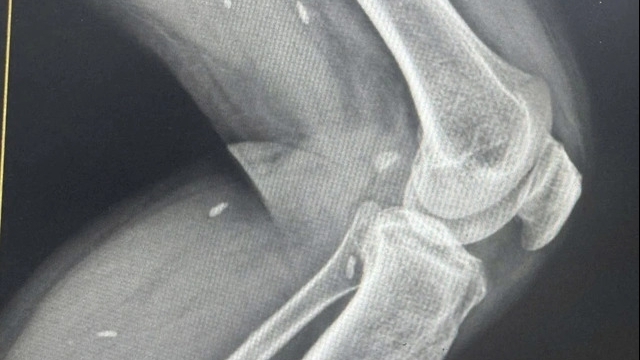

Kết quả xét nghiệm và chẩn đoán hình ảnh cho thấy tình trạng nguy hiểm của bệnh nhân: chỉ số bạch cầu tăng cao (14.6 10^9/L), hình ảnh nhiều dị vật hình xương cá nằm ngang đoạn ruột non. Kèm theo vị trí đại tràng xuống vùng hố chậu phải trong lòng có một dải tăng tỷ trọng (kích thước 24 x 6mm). Bệnh nhân được chẩn đoán thủng ruột non do dị vật, với bệnh nền bệnh phổi tắc nghẽn mạn tính và được chỉ định phẫu thuật cấp cứu.

| Hình ảnh xương cá |